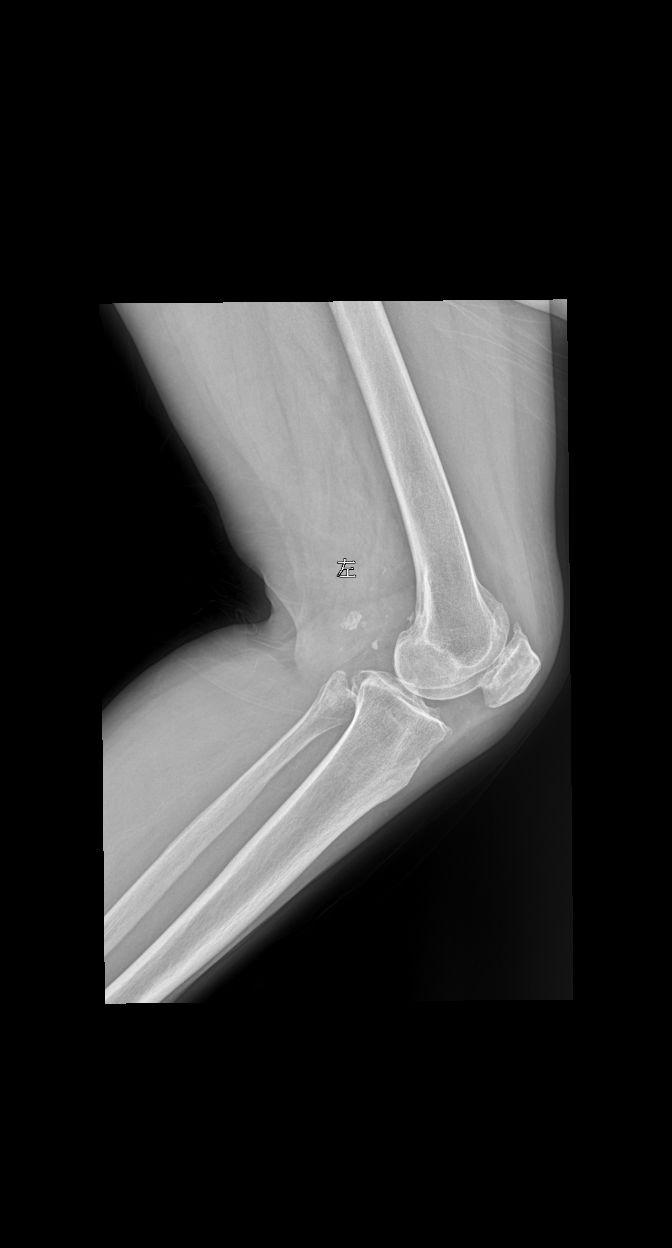

患者女 74岁行走时膝关节疼痛就诊